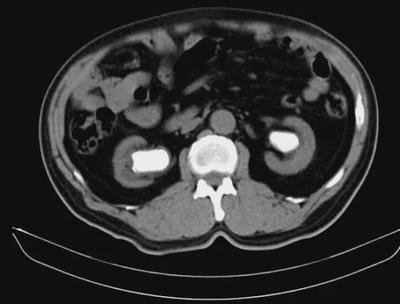

要知道,肾囊肿虽然是一个良性的囊肿,但这个良性囊肿是会持续发展的。我临床上遇到的肾囊肿患者在做复查时,身体都会出现一些很不舒服的症状,如腰酸、尿路感染、血尿、发热等。做了B超复查后,也会发现肾囊肿的体积长大了,这其实都是因为肾囊肿过大, 压迫到肾脏或出现梗阻,引发的一系列并发症表现。

一旦肾囊肿大于4厘米,压迫肾脏,就会影响到肾功能,造成患侧肾功能受损,患者会出现腰酸腰痛、乏力、腹胀、尿蛋白、血肌酐升高、尿素氮升高。而我们的肾脏有两个肾,没有患肾囊肿的一侧肾脏,会代偿患侧受损的肾脏,如果这时肾囊肿患者没有做好定期复查,就很难及时发现肾脏受损,一旦受损严重,还会导致肾衰竭。

我有一位肾囊肿患者,他最初是右侧肾长了一个囊肿,体积2厘米,无症状,也没当回事。一年过去了以后,患者发现自己总觉得乏力、腰酸,在一次体检后,发现自己血肌酐升高了,还检查出了尿蛋白(+),右肾囊肿从一个长到了3个,最大的已经长到了3厘米,左肾也被查出了囊肿,也是多发囊肿,最大的长到了2厘米。这位患者被确诊为多发性肾囊肿、肾功能不全。